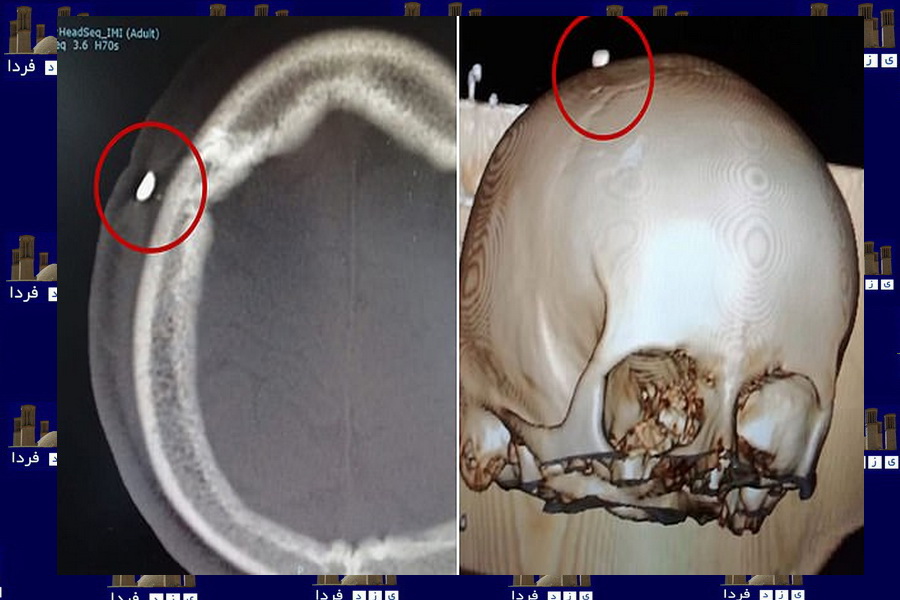

جزئیاتی از پرواز جنجالی مشهد به تهران؛ بازگشت آنتونوف؟!

طبس دقایقی بعد از برخاستن از فرودگاه مهرآباد سقوط کرد... و هیچ گاه مسافرانش را به طبس نرساند این چندمین... هواپیمای آنتونوف مسیر ...